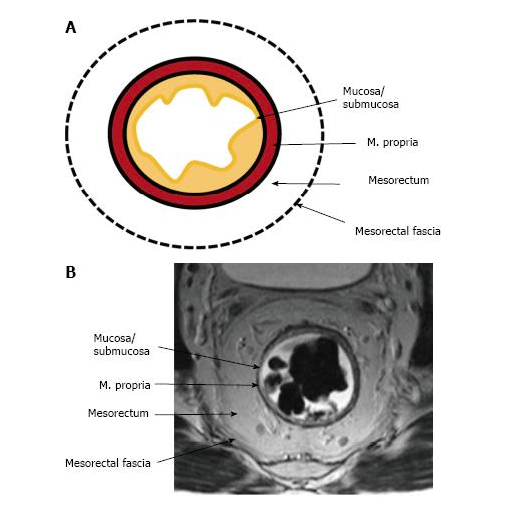

2. Giải phẫu trực tràng trên cộng hưởng từ.

Hình ảnh trực tràng trên cộng hưởng từ:

+ Lớp dịch nhầy: giảm tín hiệu ở T1w, tăng tín hiệu ở T2w.

+ Lớp niêm mạc: là lớp rất mỏng, nhận biết dựa trên hình ảnh của lớp dịch nhầy láng trên bề mặt niêm mạc và lớp dưới niêm mạc.

+ Lớp dưới niêm mạc: tăng nhẹ tín hiệu cả ở T1w, T2w và rất ngấm thuốc.

+ Lớp cơ: giảm tín hiệu cả T1w và T2w đặc biệt cơ thắt trong rất giảm tín hiệu.

+ Lớp mỡ mạc treo trực tràng: tăng tín hiệu cả T1w và T2w.

+ Lớp cân mạc treo trực tràng hoặc thanh mạc: là lớp rất mỏng, nhận biết dựa trên hình ảnh lớp cơ và lớp mỡ cân mạc treo trực tràng.

+ Hệ xương: vỏ xương mất tín hiệu cả T1w và T2w.

Hình 1. Các lớp giải phẫu của trực tràng tương ứng trên cộng hưởng từ